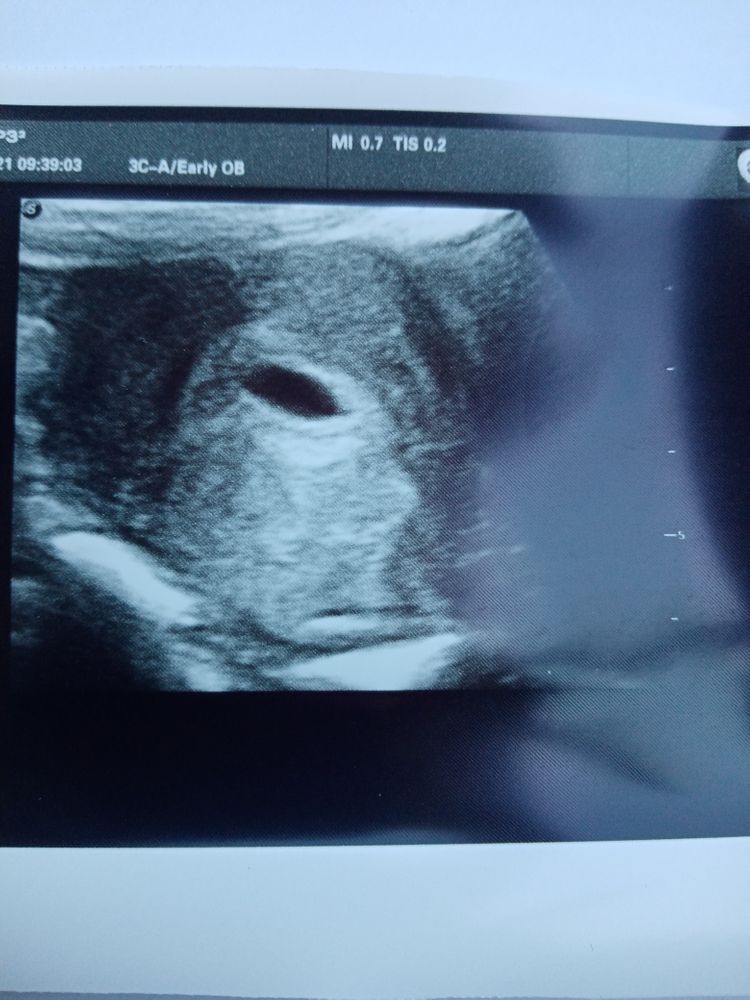

Ольга Александрова, так это срок акушерский, с первого дня последних месячных. Он не может быть другим. Ну и врач поставил срок в соответствии с размером пя Изображение

Екатерина, что-то мне кажется, что у вас срок где-то пять недель, у меня примерно в пять недель такое плодное яйцо было и только только появился желточный мешок

Alena, если приблизить, желточный мешочек есть как будто

А размер ПЯ какой?

Рита, 11мм

Екатерина, да. Нормально. У меня был ПЯ 12мм и эмбриона ещё не было. Но у меня тогда срок был ровно 5 недель. Может у вас овуляция или имплантация поздняя была.